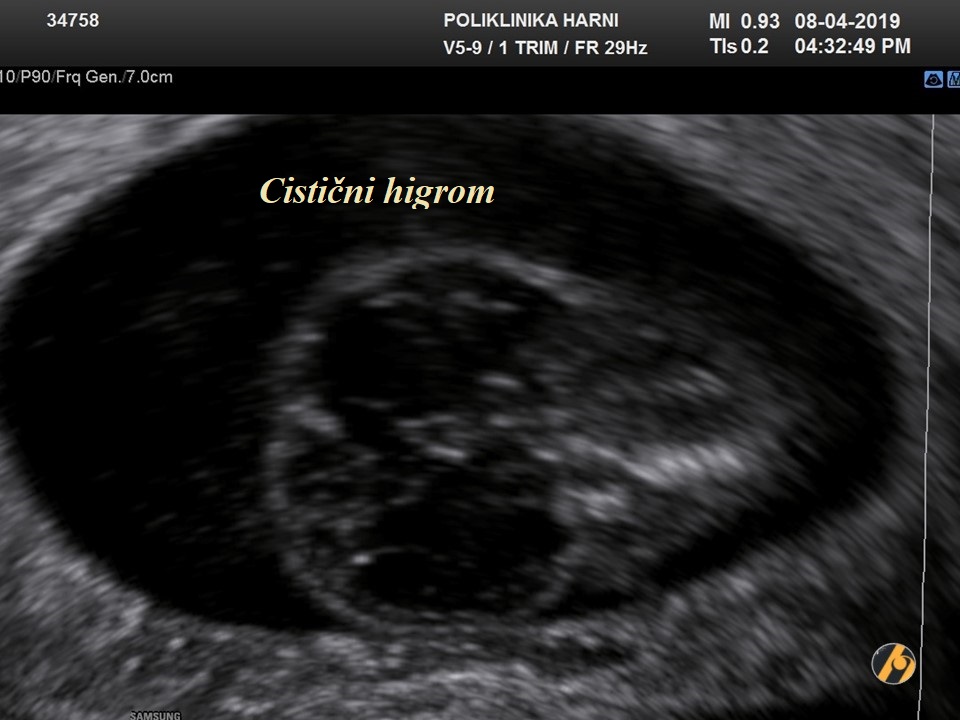

Ventrikulomegalija, definirana promjerom lateralnog ventrikula od 10 mm ili više, se nalazi u 1% trudnoća prilikom pregleda s 20.-22. tjedna.

Može biti posljedica kromosomskih i genetskih poremećaja, intrauterinog krvarenja ili urođene infekcije, iako mnogi slučajevi nemaju jasnu etiologiju. U većini slučajeva dijagnoza se postavlja u drugom tromjesečju. U prvom tromjesečju se dijagnoza može postaviti ako su koroidni pleksusi, koji obično ispunjavaju lateralne ventrikule, okruženi tekućinom.